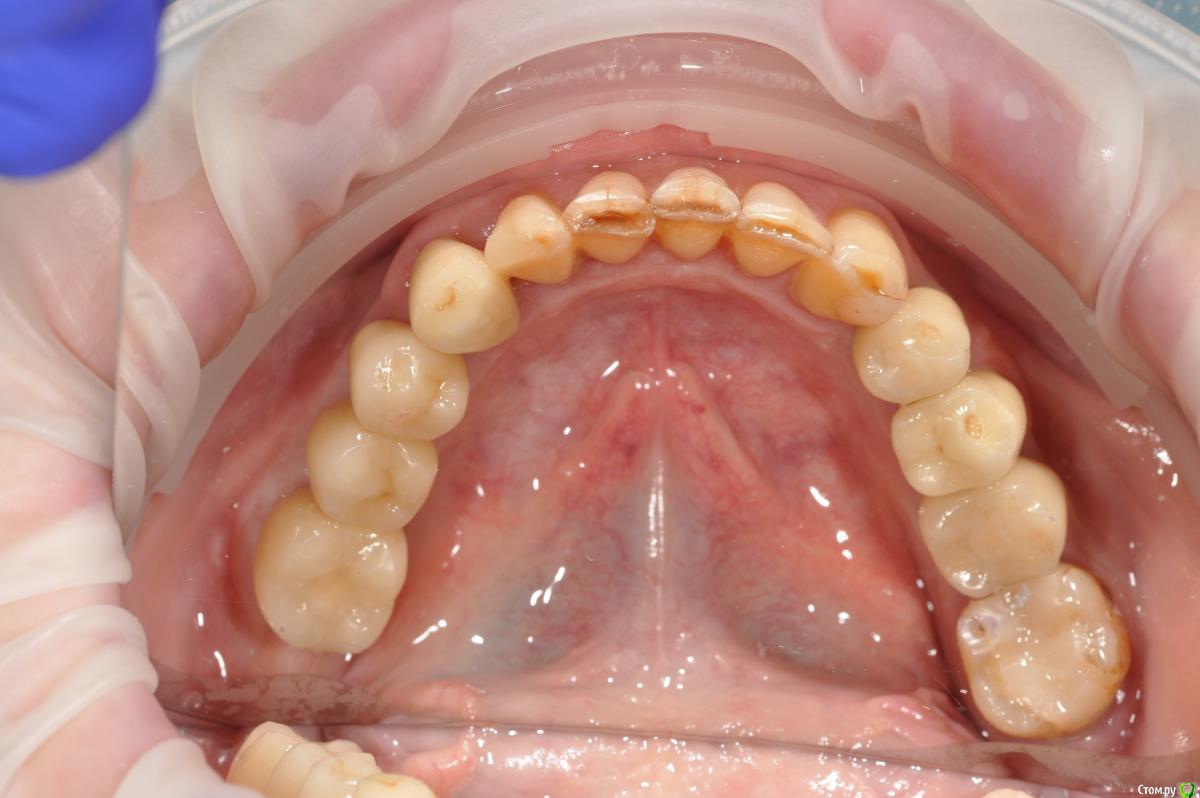

kamranchick Опубликовано 16 ноября, 2018 Поделиться Опубликовано 16 ноября, 2018 Господа, Как вы решаете вопрос с отсутствием зкпд в полном обьеме.у пациенки жалобы на то что" при поднятии языка, дна полости рта поднимается и нализиет на формирователь десны, соответственно на протезирование я пока не хочу передавать.в течении 3 недель у пациентки выросла шишка под языком в области 3 6 зуба...убрал формирователь и поставил заглушку.Видел у Ильгама как он делал зкпд, не скинете видео? не могу найтии что делать с этой шишкой и как вести пациента? спасибо 1 Ссылка на комментарий

Neilrus Опубликовано 16 ноября, 2018 Поделиться Опубликовано 16 ноября, 2018 Отсеки слизистую и подшей ниже будто сдт собираешься подсадить. С подворотом. Из сом сделай гребень. Клеить и к фдм и к зубам рядом если есть. Надо фото найти... Господа, Как вы решаете вопрос с отсутствием зкпд в полном обьеме.у пациенки жалобы на то что" при поднятии языка, дна полости рта поднимается и нализиет на формирователь десны, соответственно на протезирование я пока не хочу передавать.в течении 3 недель у пациентки выросла шишка под языком в области 3 6 зуба...убрал формирователь и поставил заглушку.Видел у Ильгама как он делал зкпд, не скинете видео? не могу найтии что делать с этой шишкой и как вести пациента? спасибодумаю до надкостницы расщепитесь со стороный переходной, подшейте как можно ниже, а к самой надкостнице полнослойный как можно плотнее пришейте, без фдм будет лучше, их потом, Каппу не забудьте на небо заранее, ибо кусочек будет нормальный.Почти похожий случай, фоткиприкрепил, не судите строго, выкладываюсь редко, прикрепленки было 1,5-2мм и то язычно 2 Ссылка на комментарий

kamranchick Опубликовано 17 ноября, 2018 Автор Поделиться Опубликовано 17 ноября, 2018 думаю до надкостницы расщепитесь со стороный переходной, подшейте как можно ниже, а к самой надкостнице полнослойный как можно плотнее пришейте, без фдм будет лучше, их потом, Каппу не забудьте на небо заранее, ибо кусочек будет нормальный.Почти похожий случай, фоткиприкрепил, не судите строго, выкладываюсь редко, прикрепленки было 1,5-2мм и то язычнону у вас ситуация понятная.... не такая тяжелая, а тут вообще ее нет, даже если бы была язычно 1.5 мм. было бы намного проще. она бы на месте оставалась бы при движении языком туда сюда, в моем случае, любое движение языком это катастрофа Ссылка на комментарий

kamranchick Опубликовано 17 ноября, 2018 Автор Поделиться Опубликовано 17 ноября, 2018 Какая толщина десны по формирователю ?стоит 4 мм формирователь, а реально десны мм 2-3 Ссылка на комментарий